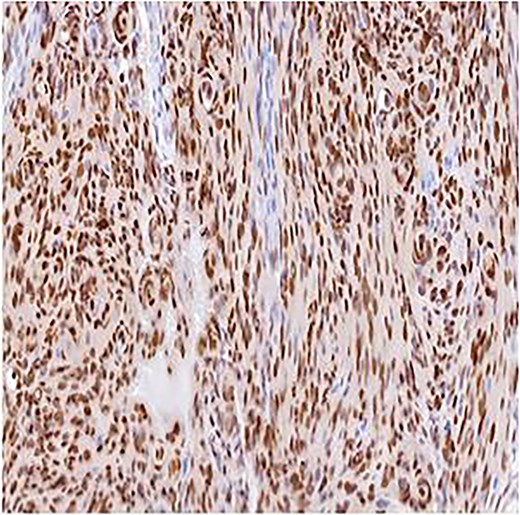

A 51-year-old woman presented in 2014 with headache and progressive right-sided weakness. MRI showed a lobulated right parietal extra-axial mass (7 × 5 × 5 cm) with homogeneous enhancement, vasogenic oedema, and midline shift. She underwent complete surgical resection followed by adjuvant radiotherapy. Histopathology demonstrated spindle-cell and meningothelial proliferation arranged in whorls with necrosis and a mitotic count of 6/10 HPF (Fig. 1). IHC was positive for EMA and vimentin but negative for cytokeratin, consistent with atypical meningioma (WHO Grade II). Ten years later, she developed progressive left-hip pain. Computed tomography (CT) of the pelvis revealed a lytic destructive lesion involving the left iliac bone with soft-tissue extension (Fig. 2). CT-guided biopsy showed tumor cells morphologically identical to the original specimen. IHC was positive for EMA and PR and negative for S-100, confirming metastatic meningioma (Fig. 3). Systemic imaging showed no visceral metastases.

Immunohistochemistry for PR, ×10. Strong nuclear staining within meningothelial tumor cells confirming meningioma differentiation.